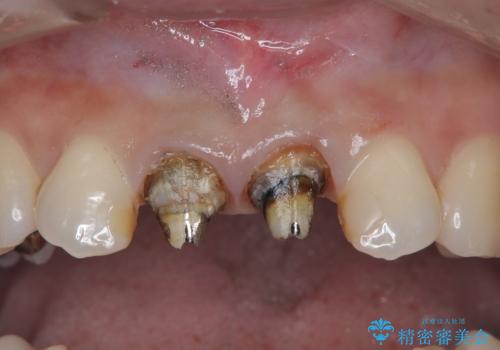

被せ物のマージンラインは歯肉縁より少し下に隠すようにしています。

- 前歯の変色を主訴に来院されました。

根管治療、土台のやりかえも提案しましたが、金銭的理由より、クラウンのみの修復としています。